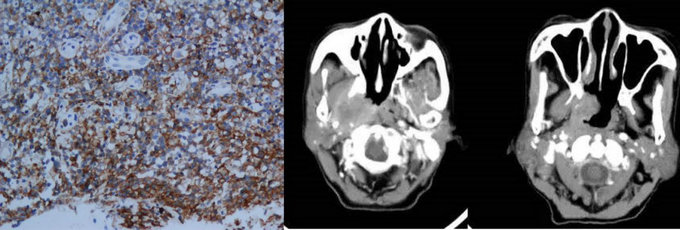

NK/T淋巴瘤病理及影像表现

但是依据Ann Arbor分期,约80%病例为局限期,而这部分局限期患者的治疗效果很差,预后不良,说明Ann Arbor分期难以准确反映结外鼻型NK/T细胞淋巴瘤的侵犯程度,对于治疗方案的选择和预后判定价值有限。肿瘤的精准分期是开展合理治疗的基础,寻找更为准确有效的分期系统,成为了目前针对NK/T细胞淋巴瘤进行精准治疗的关键前提之一。